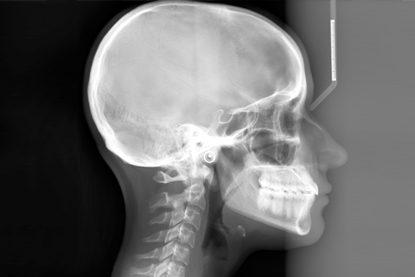

أنواع الأشعة السينية للأسنان:

سيفالوميتريك